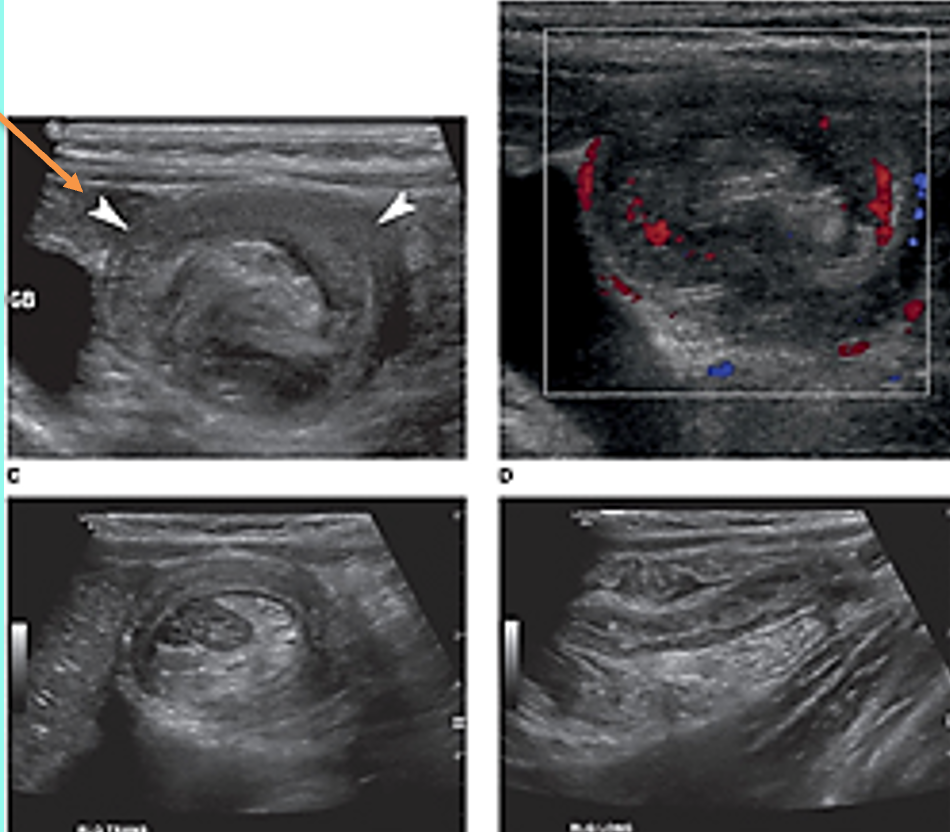

what is shown?

target or donut sign associated with intussusception

pseudokidney sign (intussusception- long axis)

sandwich sign (intussusception- long axis)